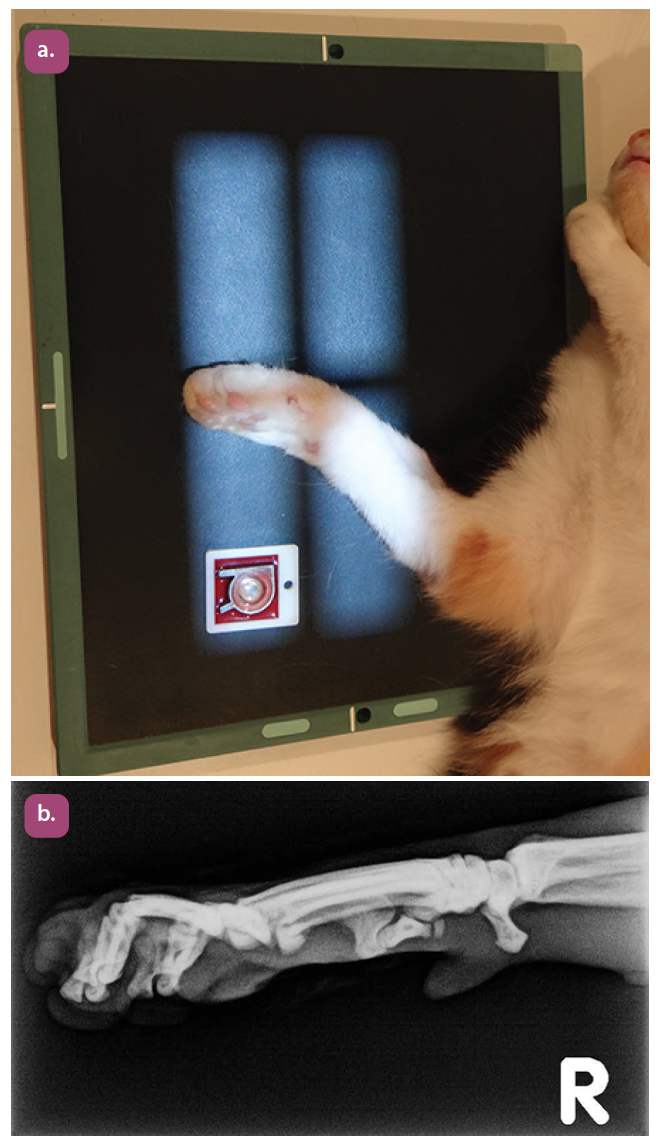

mediolateral projection of the metacarpus

mediolateral projection of the phalanges